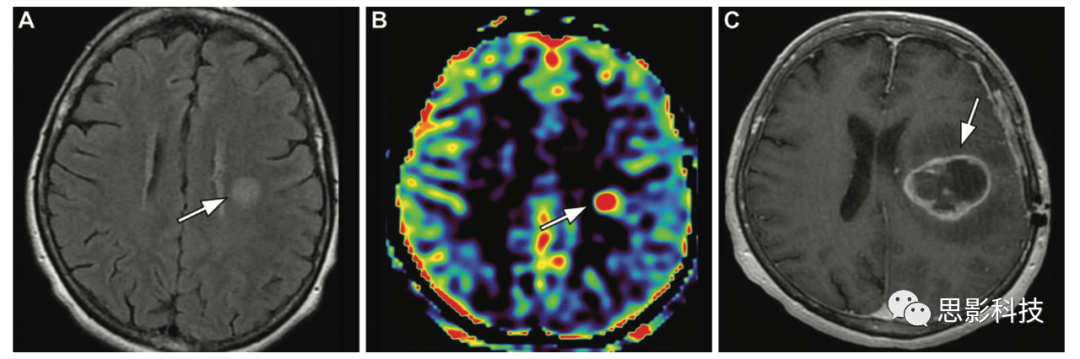

神經(jīng)膠質(zhì)瘤 ASL定量測(cè)量有助于區(qū)分高級(jí)別膠質(zhì)瘤和低級(jí)別膠質(zhì)瘤,高級(jí)別膠質(zhì)瘤因新生血管而顯示高TBF相對(duì)血流值(12),低級(jí)別膠質(zhì)瘤顯示低TBF(E5)Shen等人的研究表明,高級(jí)別膠質(zhì)瘤的絕對(duì)TBF和相對(duì)TBF均顯著高于低級(jí)別膠質(zhì)瘤(絕對(duì)TBF, 73.93±23.74 vs 38.97±17.47;相對(duì)TBF, 2.021±0.611 vs 0.971±0.268;P<0.001)。一項(xiàng)薈萃研究為ASL在膠質(zhì)瘤的術(shù)前分級(jí)診斷的準(zhǔn)確性提供了證據(jù)。研究表明,基于ASLDSC的灌注指標(biāo)具有良好的相關(guān)性和互換性。

12 一例40歲女性高級(jí)別膠質(zhì)瘤,右側(cè)偏癱15天。(AB)軸位FLAIR圖像(A)顯示左側(cè)額葉病變(箭頭),ASL(B)顯示高信號(hào)(箭頭)。(C)3個(gè)月后獲得的軸位增強(qiáng)后T1加權(quán)像顯示較大的壞死性病變(箭頭),周圍有不規(guī)則強(qiáng)化,與膠質(zhì)母細(xì)胞瘤相關(guān)。

淋巴瘤 中樞神經(jīng)系統(tǒng)淋巴瘤的初步診斷對(duì)于適當(dāng)?shù)闹委熡?jì)劃至關(guān)重要,主要是為了避免更激進(jìn)的外科手術(shù),因?yàn)榛颊呖赡軓幕熀痛髣┝糠派渲委熤惺芤妗A馨土鲈诔R?guī)序列獲得的圖像上可能無法區(qū)分,但通常不顯示實(shí)質(zhì)微血管增生。中樞神經(jīng)系統(tǒng)的原發(fā)淋巴瘤主要表現(xiàn)為血管中心生長,沒有新鮮的新生血管生成,導(dǎo)致灌注略微升高,遠(yuǎn)低于DSCASL MRI序列圖像上的高級(jí)別膠質(zhì)瘤(13)You等人基于ASL MRI的研究發(fā)現(xiàn),原發(fā)中樞神經(jīng)系統(tǒng)淋巴瘤的瘤內(nèi)和瘤周TBF相對(duì)血流值顯著低于高級(jí)別膠質(zhì)瘤(瘤內(nèi)相對(duì)TBF, 0.89±0.59 vs 2.68±1.89;瘤周相對(duì)TBF, 0.17±0.08 vs 0.45±0.28;P<0.001)

13 一例69歲男性腎功能衰竭患者發(fā)生中樞神經(jīng)系統(tǒng)淋巴瘤,表現(xiàn)為嗜睡、左側(cè)偏癱和震顫。(A)軸位彌散加權(quán)成像顯示右側(cè)顳葉軸內(nèi)浸潤性病變,彌散均勻(箭頭),腫塊效應(yīng)伴右側(cè)腦室體部受壓,中線結(jié)構(gòu)輕微左移。

(B)ASL MRI顯示右側(cè)顳葉(箭頭)高灌注。